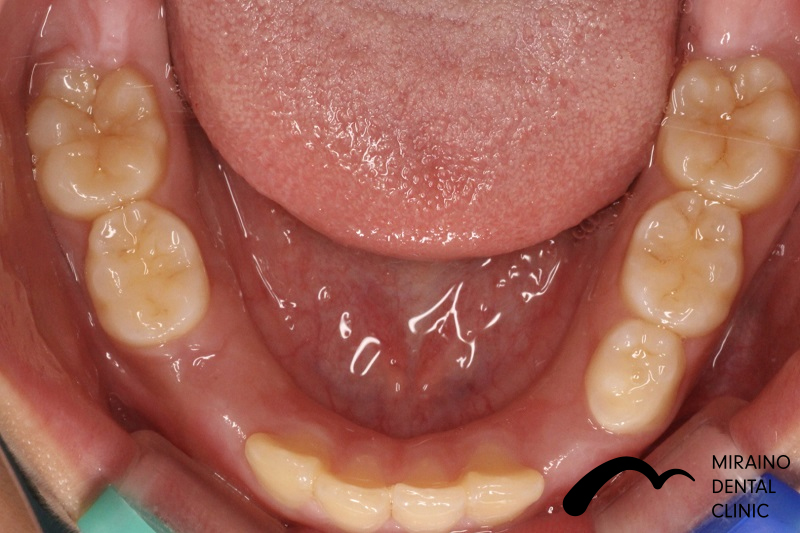

叢生(ガチャガチャ・ガチャ歯)②

| 施術名 | マウスピース矯正(インビザライン) |

| 施術の内容 | 歯科矯正でも目立ちにくい新しい矯正方法です。 透明に近いマウスピース型の矯正装置(アライナー)のため、歯に装着しても目立つことなく歯並びを矯正することが出来ます。 また、一人ひとりの合わせて矯正装置を作製いたします |

| 治療費 | インビザライン990,000円 |

| 考えられるリスク、副作用 | 疼痛・咬合時痛を生じる事があります。時間経過とともに治ります。 |

| 考えられるリスク、副作用[矯正] | 継続使用により緩んだり、外れやすくなる事があります。 割れたり壊れたりする事があります。 諸々の事情により、治療期間が当初よりも伸びる事があります。 所定の装着時間22時間を守って頂けない場合、治療計画どおりに治らない可能性があります。 歯が動く際に、痛みが出る事があります。 矯正期間中は虫歯や歯周病のリスクが高まりますので、しっかりとしたケアが必要です。 歯の移動に伴う歯肉退縮や歯根吸収が起こる事があります。 インビザライン・システム(invisalignR)は、アメリカのアラインテクノロジー社より提供されている、カスタムメイドの矯正装置ならびに、これを用いた治療システムを指します。 インビザラインを用いた治療は保険適用外の自由診療となります。 厚労省の認可(医薬品医療機器等法上の承認)は得ていないため、まだ明らかになっていないリスクが存在する可能性があることをご了承ください。 |

| 全て | 必ずしもご希望通りの見た目にならない事があります。 |